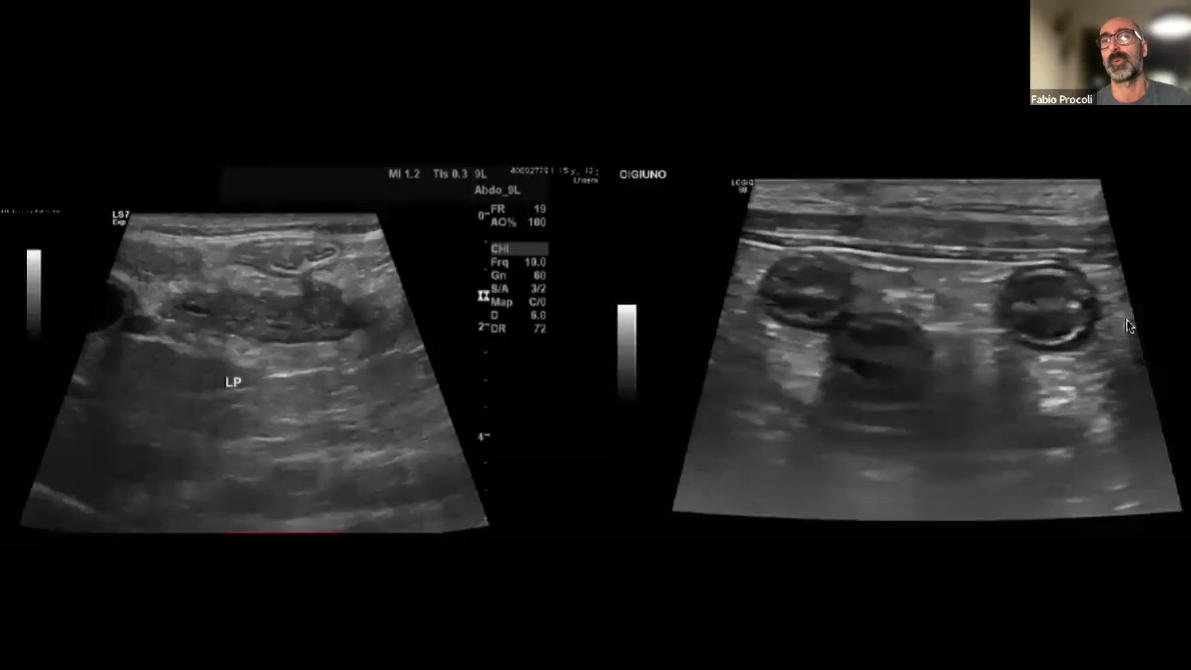

Хронічна хвороба нирок у собак і котів Назад Ознайомтесь з відео Документальні фільми Лікування артриту у собак за допомогою раціону JM Joint Mobility Документальні фільми Хронічна хвороба нирок у собак і котів Документальні фільми Хронічна діарея у собак і котів. Лекція для ветеринарних спеціалістів Документальні фільми Харчові алергії у собак і котів. Лекція для ветеринарних спеціалістів